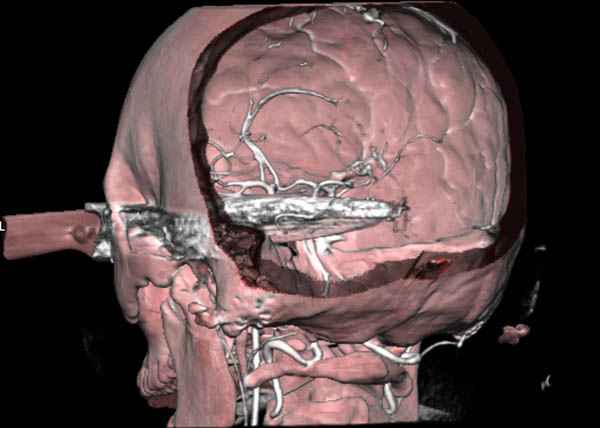

В своих выступлениях я рассказывал, что наши центры в мирное время по пенетрирующим травмам не уступает Ираку или Афганстану, и вот недавно к нам поступила больная 22 лет, травма "ножом в глаз" от бывшей подруги нынешнего "бой френда".

При поступлении в сознании, жаловалась на неприятные ощущения в глазнице.

По протоколу сделаны все необходимые исследования: рентген, ангиограмма с 3Д реконструкцией, где обнаружили что все жизненно важные сосуды не задеты, даже некоторые "сидят" изгибаясь на ноже.

Одним махом нож удалить не удалось, пришлось раскачать и потом двумя руками удалили нож. Рана без кровотечения, обработана и зашита.